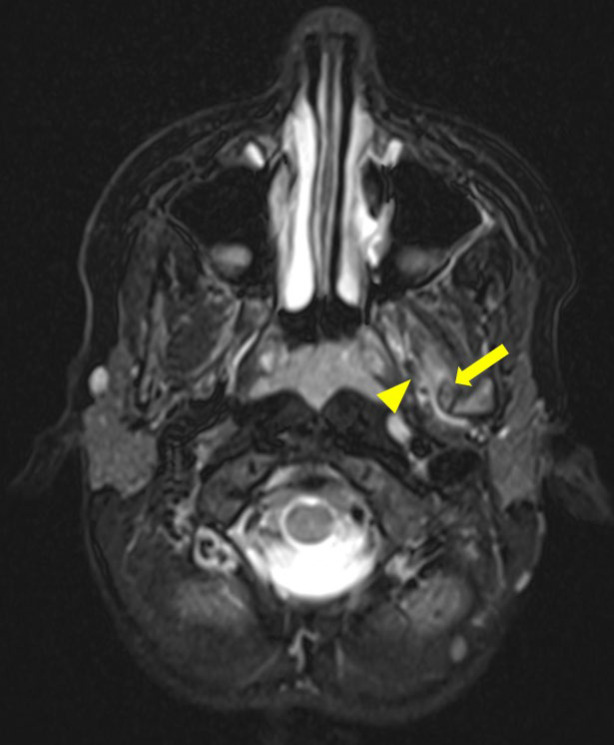

本报告报告一例非常罕见的8岁儿童,由蝶下颌韧带钙化引起的进行性限制开口(牙关)。这个病例突出了与这种疾病相关的诊断和治疗挑战的困难。我们讨论了详细的临床和放射学方法,包括用于识别钙化的成像技术,以及所选择的治疗方案,即颌面物理治疗。本报告提供了新的信息,现有文献对这种罕见的实体和提供有用的信息,临床管理类似的情况下。教学要点:蝶下颌韧带骨化症是一种非常罕见的导致张嘴受限的原因,也是一种具有挑战性的诊断。

This report aims to present a very rare case of progressive limited mouth opening (trismus) in an 8‑year‑old child caused by calcification of the sphenomandibular ligament. This case highlights the difficulty of diagnostic and therapeutic challenges associated with this disorder. We discuss the detailed clinical and radiological approach, including the imaging techniques used to identify the calcification, as well as the treatment option chosen, namely maxillofacial physiotherapy. This report provides new information to the existing literature on this rare entity and to provide useful information for the clinical management of similar cases. Teaching point: Sphenomandibular ligament ossification is a very rare cause of limitation of mouth opening and can be a challenging diagnosis.